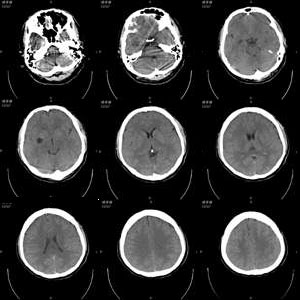

患者男,21岁,外伤时发现右侧基底节区有低密度影,问了既往史,无异常